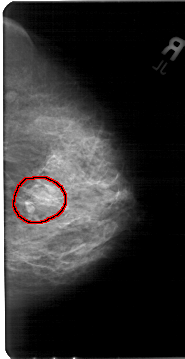

A_1397_1.LEFT_MLO

LEFT_MLO LINES 5491 PIXELS_PER_LINE 2926 BITS_PER_PIXEL 12 RESOLUTION 43.5 OVERLAY

FILE: A_1397_1.LEFT_MLO.OVERLAY

TOTAL_ABNORMALITIES 1

ABNORMALITY 1

LESION_TYPE MASS SHAPE LOBULATED MARGINS OBSCURED

ASSESSMENT 4

SUBTLETY 3

PATHOLOGY BENIGN

TOTAL_OUTLINES 1

BOUNDARY